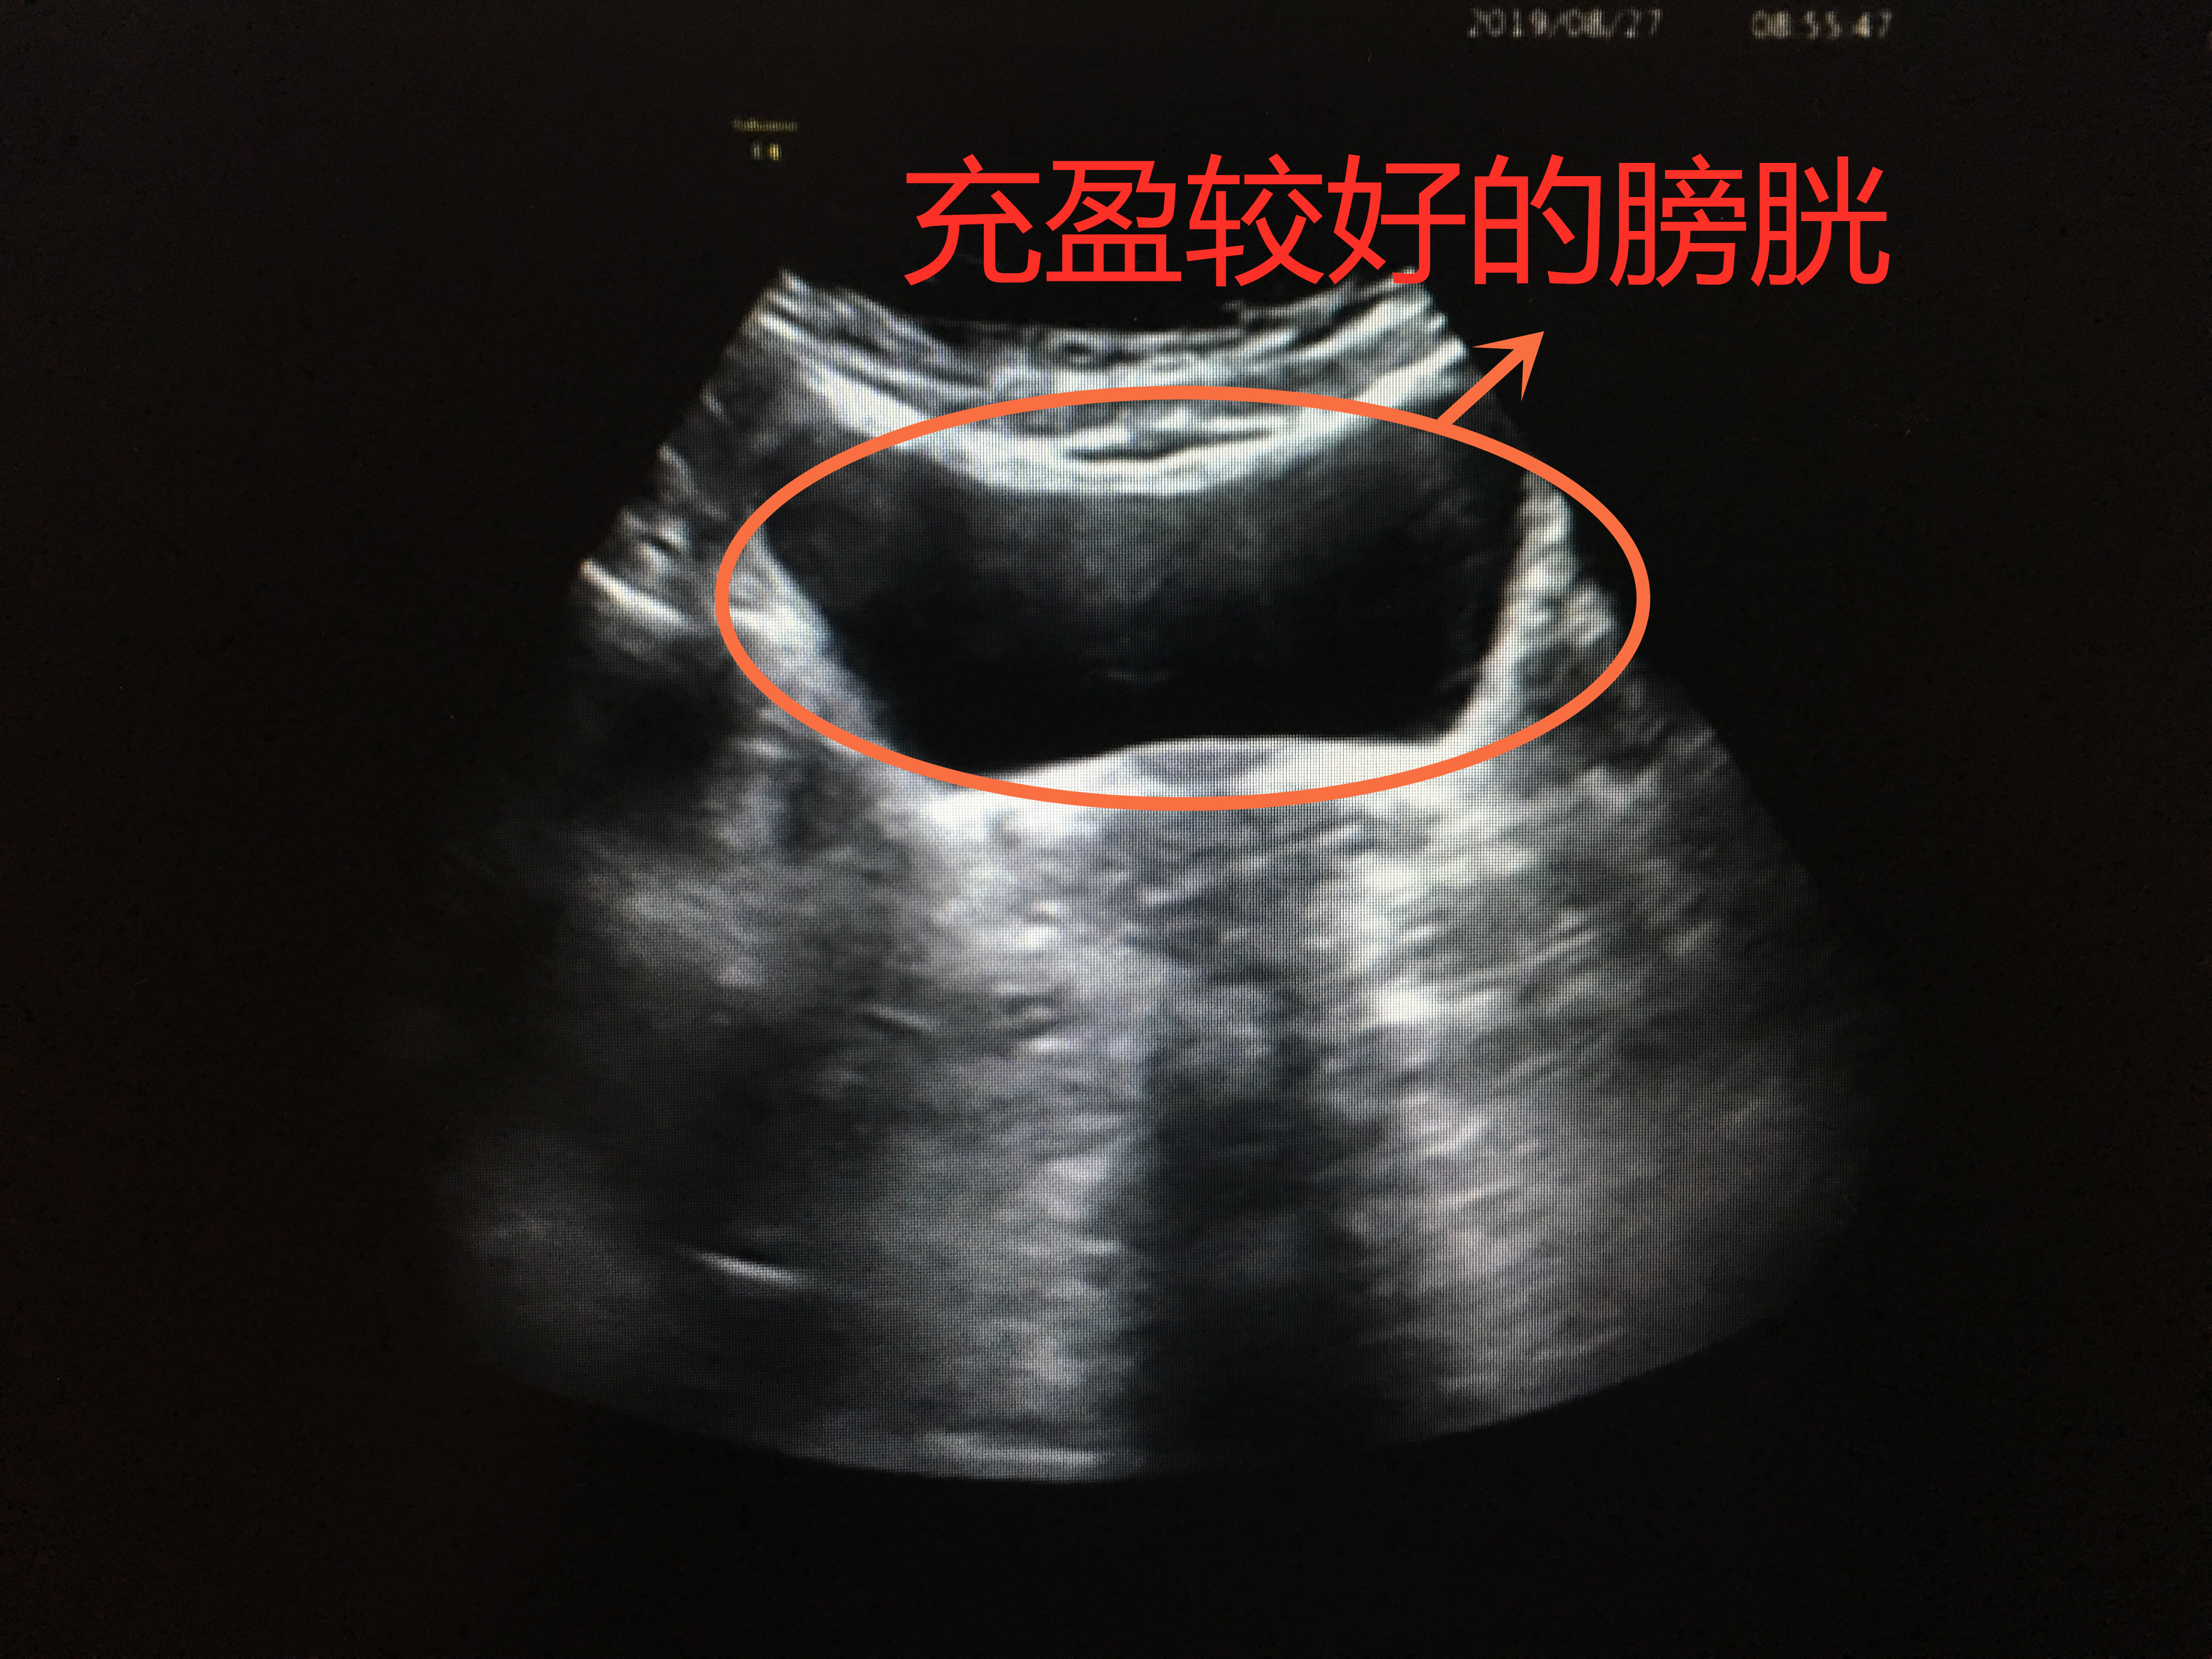

憋尿较好,膀胱充盈

憋尿欠佳,膀胱欠充盈

膀胱就像一个皮球,当你往里面打足气时,皮球便充分撑开;而当打的气不够时,皮球就瘪着。所以,当你憋尿充足时,膀胱充盈起来,把每个角落都撑开,检查时便一览无遗;当憋尿不够,充盈欠佳时,局部可能皱褶起来,隐藏病灶。所以,下次医生让你憋尿的时候,就努力的憋吧。